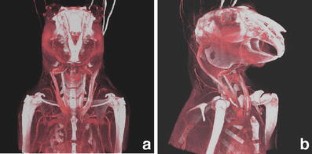

Flat-panel volume computed tomography (fpVCT) is a recent development in imaging. We discuss some of the musculoskeletal applications of a high-resolution flat-panel CT scanner. FpVCT has four main advantages over conventional multidetector computed tomography (MDCT): high-resolution imaging; volumetric coverage; dynamic imaging; omni-scanning. The overall effective dose of fpVCT is comparable to that of MDCT scanning. Although current fpVCT technology has higher spatial resolution, its contrast resolution is slightly lower than that of MDCT (5-10HU vs. 1-3HU respectively). We discuss the efficacy and potential utility of fpVCT in various applications related to musculoskeletal radiology and review some novel applications for pediatric bones, soft tissues, tumor perfusion, and imaging of tissue-engineered bone growth. We further discuss high-resolution CT and omni-scanning (combines fluoroscopic and tomographic imaging).